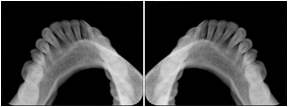

3. A dental provider wishes to capture a series of DICOM IO images for the patient’s dentition. The tooth morphology, teeth are divided into molars, premolars, canines and incisors, and a number of images for each jaw. The anatomic information was captured utilizing the triplet of schema. This standard code sequence is based on ISO 3950-2010, Dentistry - Designation system for teeth and areas of the oral cavity.

Every IO image should have anatomic information either through the primary or modifier sequence.

In most standard cases, images are oriented in structured layouts. These structured displays are useful to be shared between providers for reference purposes.

Table OO.1.1-1 shows structured display standard templates, where Viewset ID is based on the Japanese Society for Oral and Maxillofacial Radiology (JSOMR) classification provided by JIRA (Japan Medical Imaging and Radiological Systems Industries Association, www.jira-net.or.jp). Expected or typical teeth to be imaged location, region and designation codes are based on ISO 3950-2010, Dentistry - Designation system for teeth and areas of the oral cavity. For all the hanging protocols listed in OO.1.1-1, the value to use for Hanging Protocol Creator (0072,0008) is "JSOMR" and the value to use for Hanging Protocol Name (0072,0002) does not include "JSOMR" (e.g., "DL-S001A", not "JSOMR DL-S001A").